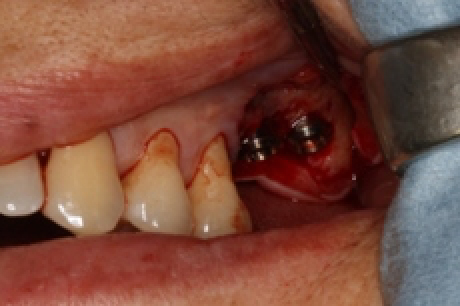

歯を抜いた後です。炎症により、大部分の骨が吸収しております。

予定通り、インプラントを埋入しました。使用インプラントはプラトンタイプ4です。